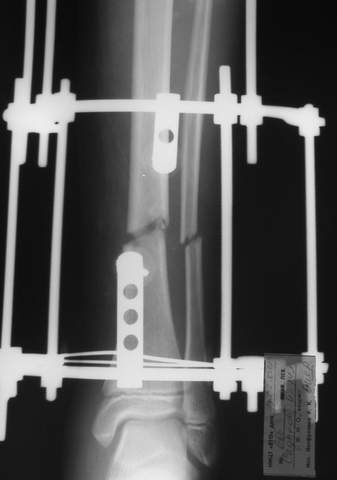

3a

3b

3c

В аттачте № 3 - один из примеров полукольцевого аппарат...

Это уже я баловался.

Итог? Работы больше (по времени и

интраоп "подгонке"), срастается также, а особого преимущества по сравнению с

"чиста" кольцевым (вес, удобство ношения и пр.) - я, по крайней мере,

не нашел.

Теперь не балуюсь.

Может быть зря?

;-)